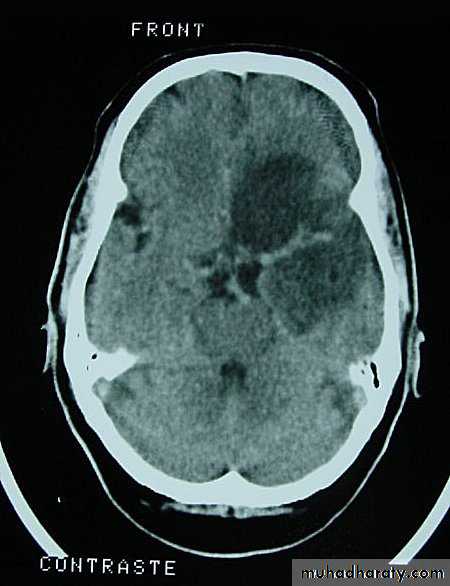

Metastatic Brain Tumours Post contrast CT

• On CT, they only show well with intravenous contrast.